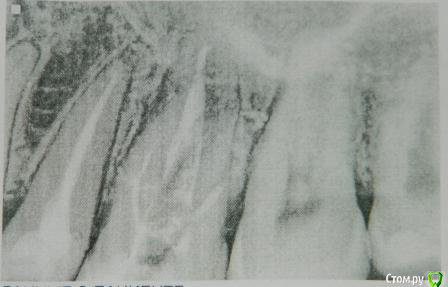

ИринаШафигуллина Опубликовано 12 февраля, 2015 Поделиться Опубликовано 12 февраля, 2015 Здравствуйте, уважаемые стоматологи!Пожалуйста, помогите советом!26 зуб.В сентябре 2014г резко заболел и буквально за 1 сутки умер.На первом приеме мне его раскрыли, удалили "мертвые" нервы, прочистили каналы и 1 неделю я полоскала содо-солевым раствором.Потом положили пасту метапекс и закрыли временной пломбой.Через месяц зуб снова воспалился, процедуру повторили. Потом еще месяц, снова воспаление, снова паста и временная пломба...И так 4 раза.И сегодня мне врач говорит " я считаю, что дальнейшее лечение бесполезно и предлагаю удалить Вам зуб".На данный момент зуб особо не беспокоит, но в щеке есть небольшое уплотнение, а когда по зубу стучишь, боли нет.Мне жаль потраченных денег, нервов и так просто сдаваться я не хочу)))Пошла сегодня еще в 2 клиники на консультацию.В одной мне объяснили, что 1 канал из 3х кривой, и его неправильно просверлили, и поэтому лечебная паста туда не попадает и воспаление продолжается.А во второй сказали что уплотнение в щеке есть, но причину они установить не могут, а воспаления в корневых каналах нет, но лечение предлагают то же самое(снова все прочистить, метапекс и временная пломба).И вот я не знаю что делать.Удалять мне этот зуб или все же продолжать лечить?Если метапекс за 4 раза не помог, есть ли шансы, что он поможет в 5 раз?...И что мне делать с этим уплотнением?Какие антибиотики прописывают в таких случаях?Опухла щека 2 недели назад.На десне есть небольшая красноватая припухлость, но основная боль внутри в щеке...Видимая снаружи опухоль спала на 3 день...А вот неприятные ощущения при накусывании остались(мне кажется связано именно с этим уплотнением).Может надо чем-то полоскать? Ссылка на комментарий

Гарриевич Опубликовано 12 февраля, 2015 Поделиться Опубликовано 12 февраля, 2015 1- зуб не удалять, по крайней мере по снимку и жалобам причин для удаления нет2- дело не в метапексе, а в предшествующей ему подготовке и очистки корневых каналов от инфекции3- уплотнение это следствие, а не причина4- антибиотики не нужны5- полоскание не поможет и не может в данном случае помочь в принципе Вам нужно найти грамотного врача, который работает с коффердамом, желательно с увеличением и совестью 1 Ссылка на комментарий